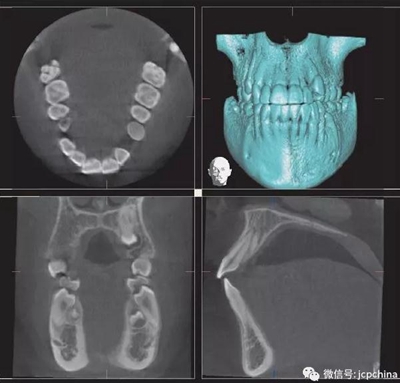

(6)運(yùn)動(dòng)偽影

這個(gè)比較常見(jiàn),小編就不解釋了。